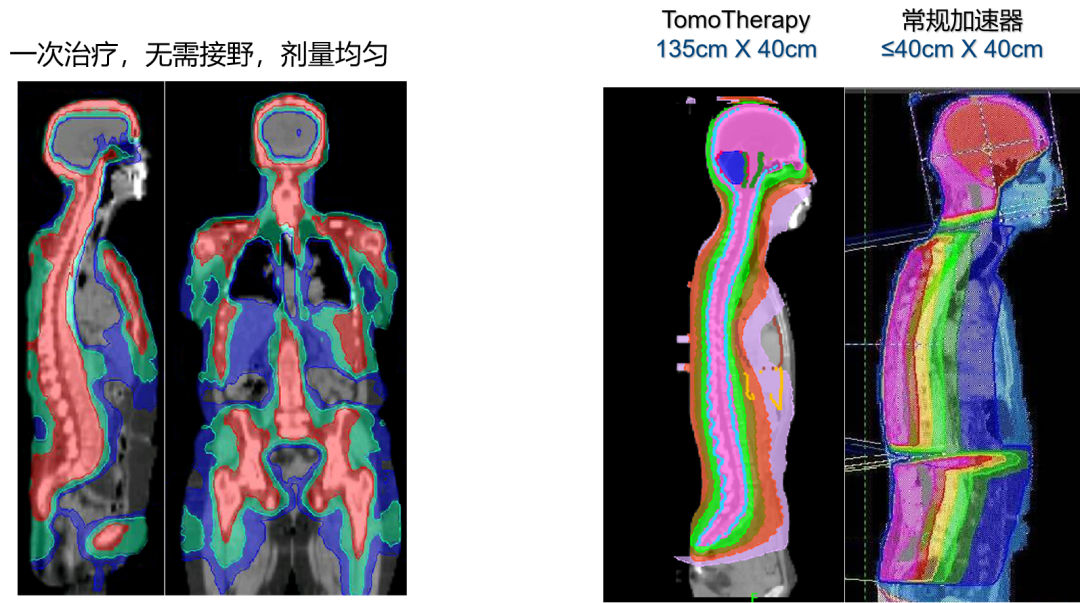

超大照射范围

照射范围达135厘米乘以40厘米,轻松应对全脑、全脊髓等大范围治疗,满足复杂肿瘤的治疗需求。

多发病灶及大肿瘤

对于超出普通加速器治疗范围、常规放疗难以同时覆盖的全身多发病灶及病变较长的大肿瘤,TOMO放疗能够实现连续且同步的照射。